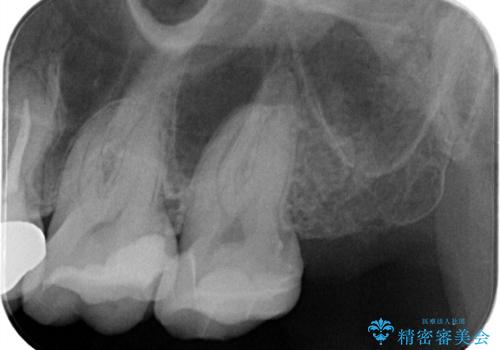

- 定期検診にて虫歯が見つかった患者様です。

金属のインレーの下と、歯と歯の間も虫歯だったため、つなげた形でセラミックインレーにて修復を行なっています。

e-max プレスインレーを用いることで、適合の良い治療ができます。